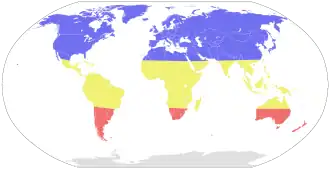

A gripe atinge o momento de maior prevalência durante o inverno. Uma vez que os invernos do hemisfério norte e sul ocorrem em diferentes alturas do ano, existem anualmente duas estações de gripe. Por este motivo, a Organização Mundial de Saúde faz recomendações para duas formulações de vacina em cada ano, uma para cada hemisfério.[98]

No entanto, também se verificam variações sazonais nas taxas de infeção de regiões tropicais. Em alguns países, os picos de infeção são observados principalmente durante a estação das chuvas.[144] As alterações de contacto em função dos períodos escolares, que são um dos principais factores de transmissão doenças infantis como o sarampo ou a tosse convulsa, podem também ter algum papel na transmissão de gripe.[145] A estirpe H5N1 apresenta sazonalidade não só em seres humanos, como também nas aves.[146]